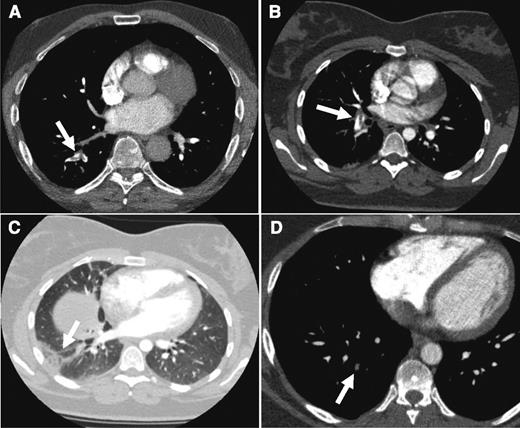

CTPA results from the cases. CTPA of patients from case 1 (A: arrow indicates acute thrombus in segmental artery to the right lower lobe), case 2 (B: despite breathing artifacts, clear visualization of acute PE in right segmental artery; C: arrow shows a wedge-shaped peripheral consolidation indicative of pulmonary infarction), and case 3 (D: arrow points to an organizing mural thrombus in a right basal segmental pulmonary artery).

The third patient is a 52-year-old man with a prior history of an unprovoked acute bilateral PE 4 years ago. He noticed a progressive sharp pain on the left side of his back with every deep breath. Initially, he thought that he had torn a muscle while painting his garden house. Since his symptoms persisted for 2 days and he recognized this particular pain from his first thromboembolic episode, he decided to visit his general practitioner who referred him to our outpatient clinic to rule out recurrent PE. Physical examination revealed no abnormalities. Chest radiograph and ECG were normal as well. His pain could be provoked by firm pressure on the seventh and eighth left ribs. Consequently, a musculoskeletal cause of the pain was judged most likely, although recurrent PE could not be ruled out. Both the Wells rule (1.5 points for previous PE) as well as the revised Geneva score (3 points for previous PE) indicated PE unlikely. Because the subsequently assessed d-dimer level was 910 µg/L, the patient was referred for CTPA, which showed 1 small organizing mural thrombus in a right basal segmental pulmonary artery. No intrapulmonary or ossal irregularities were observed. Since his first acute PE was confirmed in a different hospital, we had no earlier CTPA results for comparison. Nonetheless, the radiologist’s final conclusion was “no signs of an acute pulmonary thrombus, only evidence of residual emboli.” At this point, can we safely discharge this patient without anticoagulant treatment?